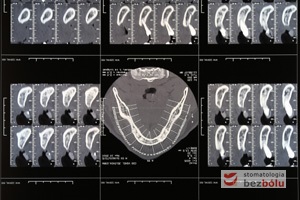

Radiologiczny obraz jamy ustnej z wykorzystaniem tomografu - precyzyjne pozycjonowanie lokalizacji planowanych implantów

Radiologiczny obraz jamy ustnej z wykorzystaniem tomografu – precyzyjne pozycjonowanie lokalizacji planowanych implantów